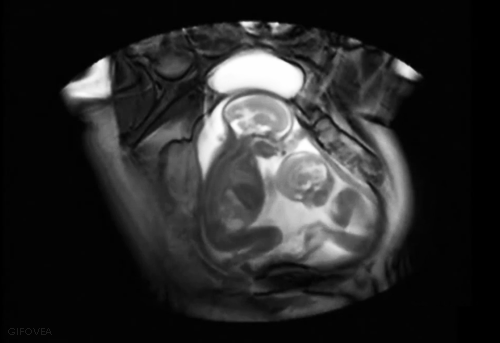

En 2011, los investigadores del equipo de Umberto Castiello de la Universidad de Padua analizaron vídeos en 3D de gemelos en el vientre de su madre. En la semana 14 de gestación, los gemelos se acercaban entre sí. En la semana 18, se tocaban con más frecuencia. Los investigadores afirmaron que el estudio cinemático de las grabaciones reveló que los gemelos se hacían gestos diferentes y que, al tocar la zona delicada del ojo, lo hacían con tanta suavidad como cuando se acariciaban su propio rostro.